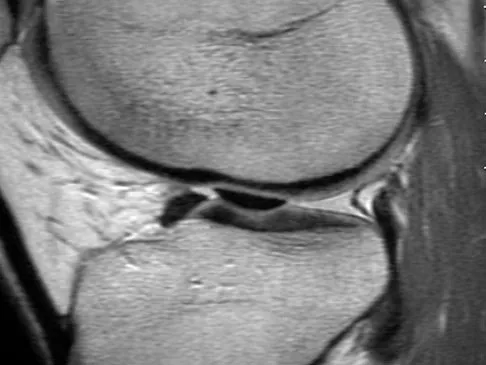

Question 71High Yield

A 21-year-old soccer player reports pain and is unable to straighten his knee following an acute injury during a game. He is unable to continue to play. An MRI scan is shown in Figure 3. What is the next most appropriate step in management?

Explanation

The patient has a locked knee that cannot be fully extended. This is most likely the result of the mechanical block of a bucket-handle tear that has flipped into the notch. Also, the pain may be so severe that the muscle spasm prevents the knee from straightening out. When the patient is anesthetized, the muscle spasm relaxes and the meniscus can be reduced out of the notch. Arthroscopy is the treatment of choice. A meniscal repair is usually possible in large bucket-handle tears because the meniscus is torn in the red-red zone where most of the vascular supply is located. If the handle portion is badly frayed or damaged, a partial meniscectomy should be performed. The classic finding on MRI is a "double PCL sign." This is due to the flipped portion of the meniscus in the notch. Critchley IJ, Bracey DJ: The acutely locked knee: Is manipulation worthwhile? Injury 1985;16:281-283.